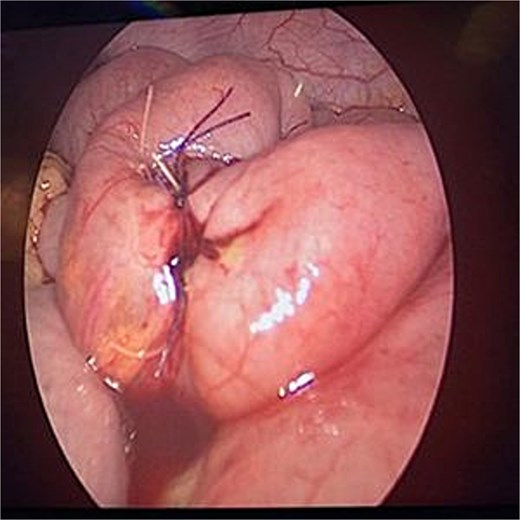

The patient was stabilized with IV fluids, nasogastric decompression, and antibiotics. Emergency laparoscopic surgery was performed using a trans-umbilical Hasson technique for camera access and two 5 mm working ports. Intraoperative findings included a foreign body lodged in the proximal jejunum without adhesions. Transparietal suspension sutures were used to facilitate exposure. Enterotomy was performed, and the object was extracted via an endo-bag. The enterotomy site was closed using STRATAFIX™ 3.0 suture (Figs 2 and 3). A laparoscopic appendectomy was concurrently performed via the umbilical incision using the in-out technique (Fig. 4).